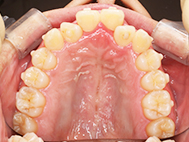

After

装着が目立ちたくないとの事でアライナ-での矯正を希望されました、歯の間を削り少し歯の幅をスリムにして綺麗なアーチに並びました。